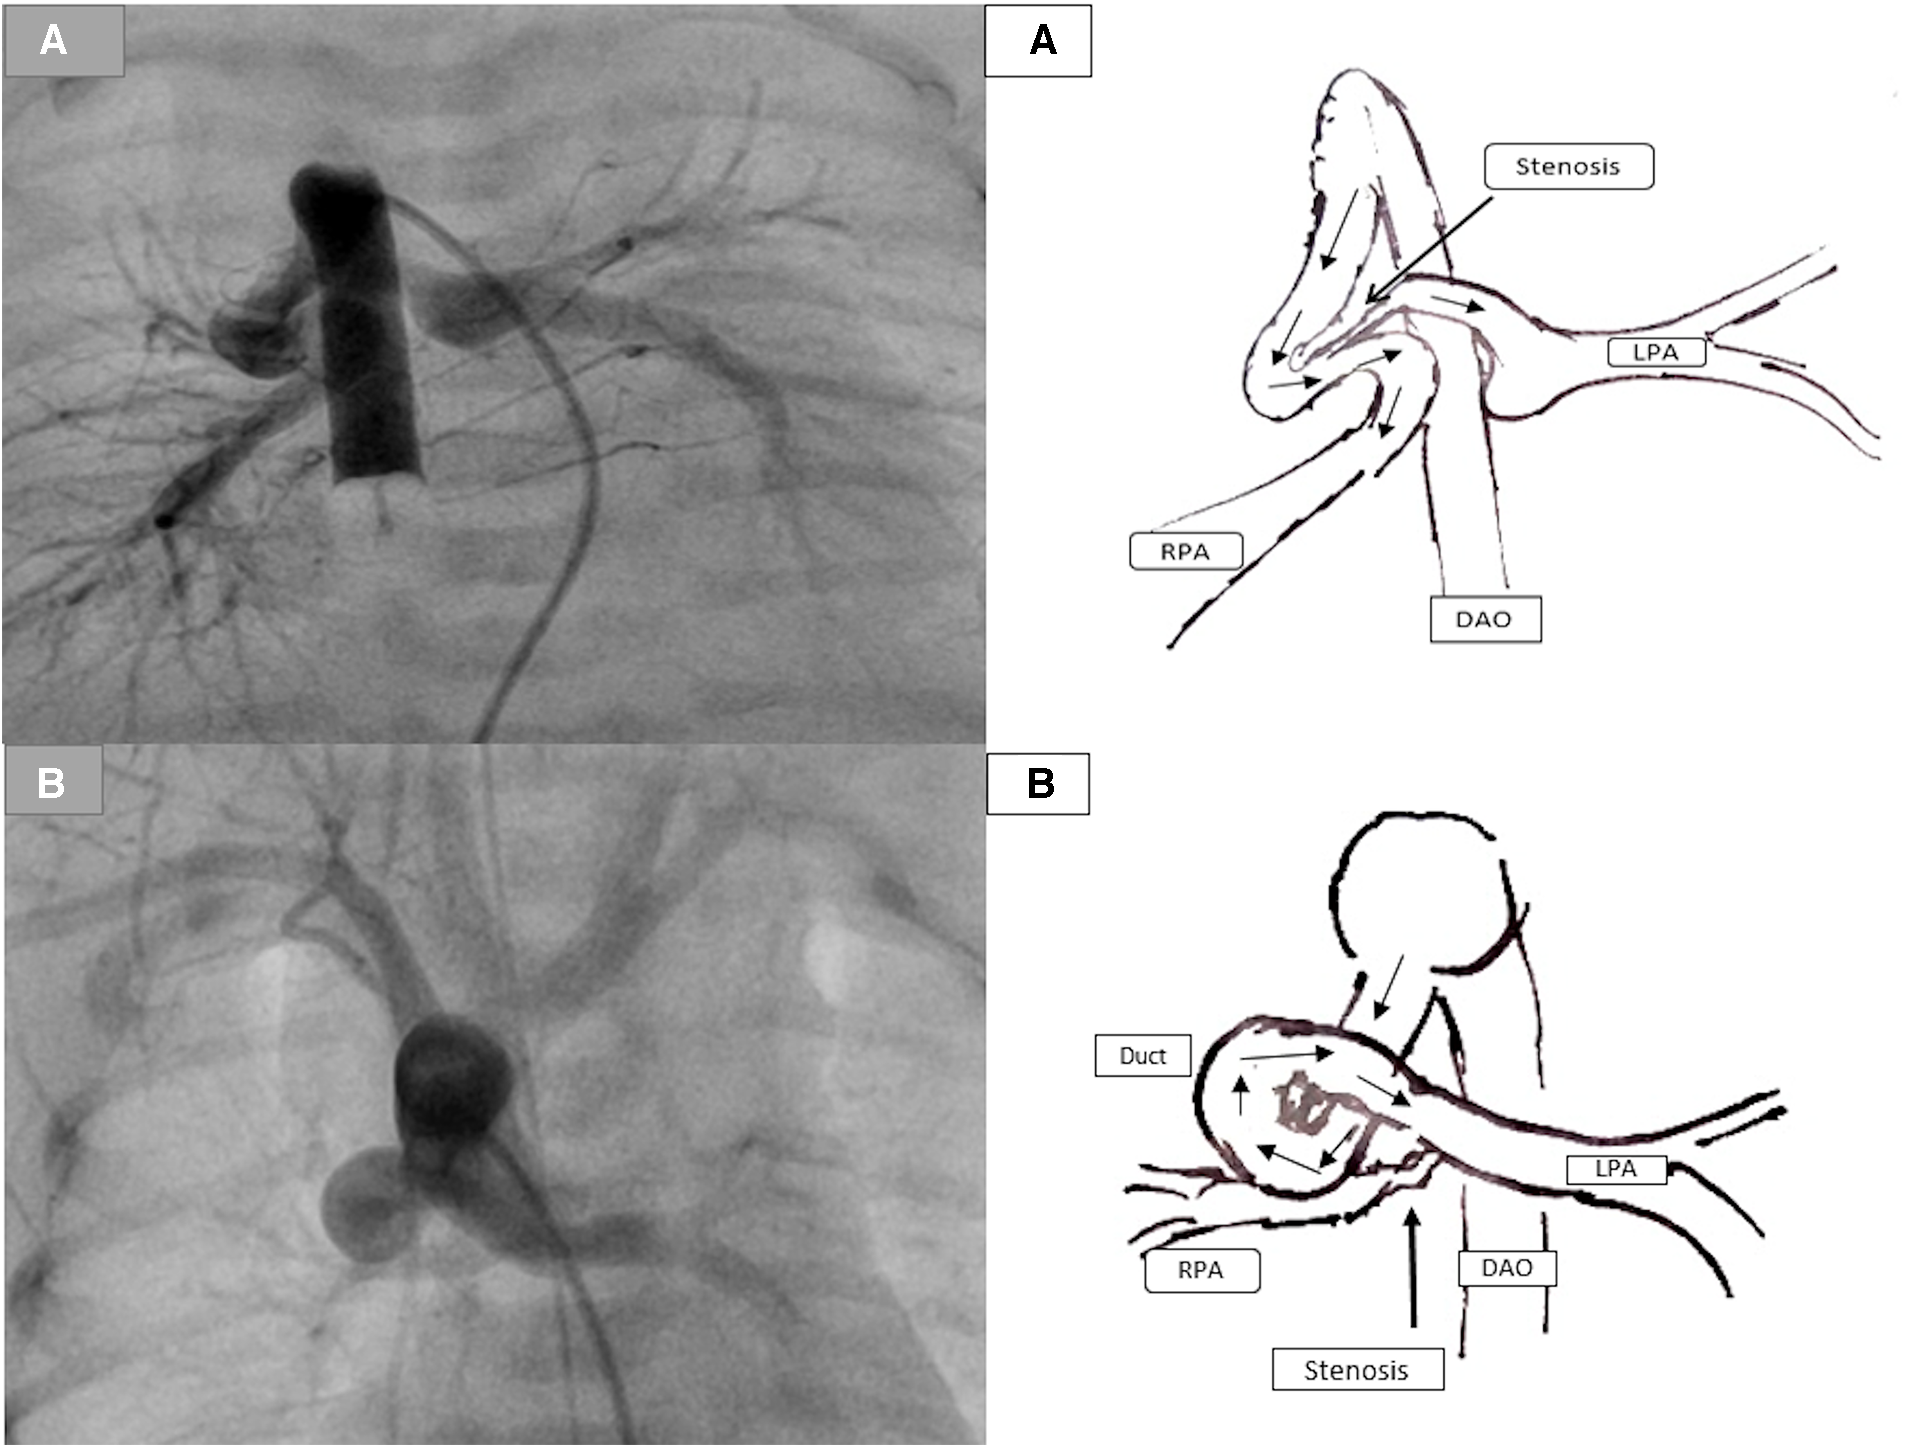

Figure 3

Demonstration of the duct-associated pulmonary stenosis. (A) represents a tortuous duct with two curves with significant pulmonary stenosis (PS) caused by the ductal tissue. (B) represents a tortuous duct with complex curves and significant RPA stenosis.

Figure 4

Demonstration of two stents in a duct with mild bilateral pulmonary stenosis. (A) Duct originates from the aortic arch and inserts into the pulmonary arteries without the pulmonary trunk. (B) Two duct stents were implanted and inserted into both arteries. The orange arrow represents the distance required to reconstruct the pulmonary arteries. In contrast, the black arrow represents the pulmonary segments that were surgically resected by removing the stents after the ductal stent. (C) The orange arrow for the same patient represents the underdeveloped central pulmonary arteries after the resection of stents and the pulmonary reconstruction.